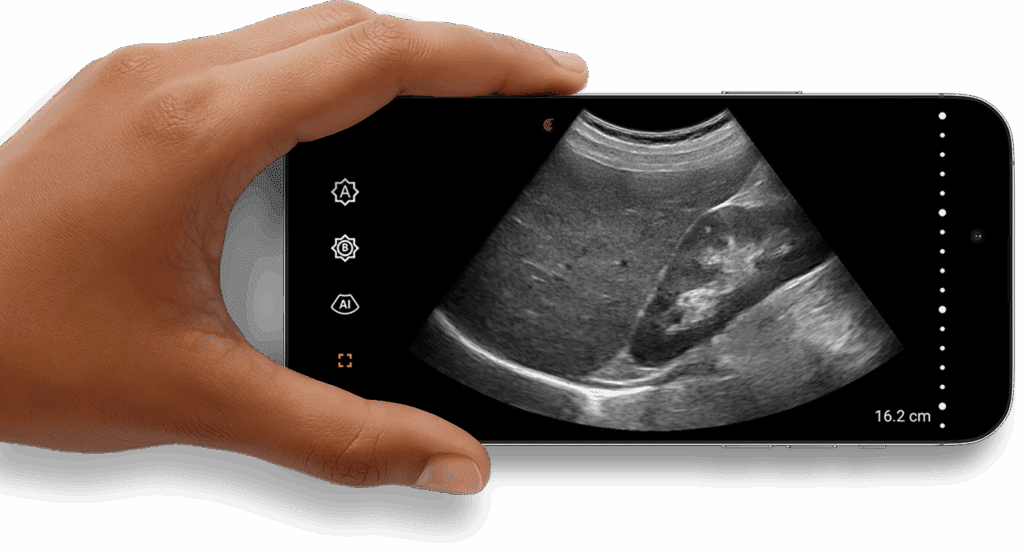

Images et

Intelligence à Emporter

Votre téléphone et Clarius sont tout ce dont vous avez besoin pour emporter la puissance de l'échographie partout où vous allez.